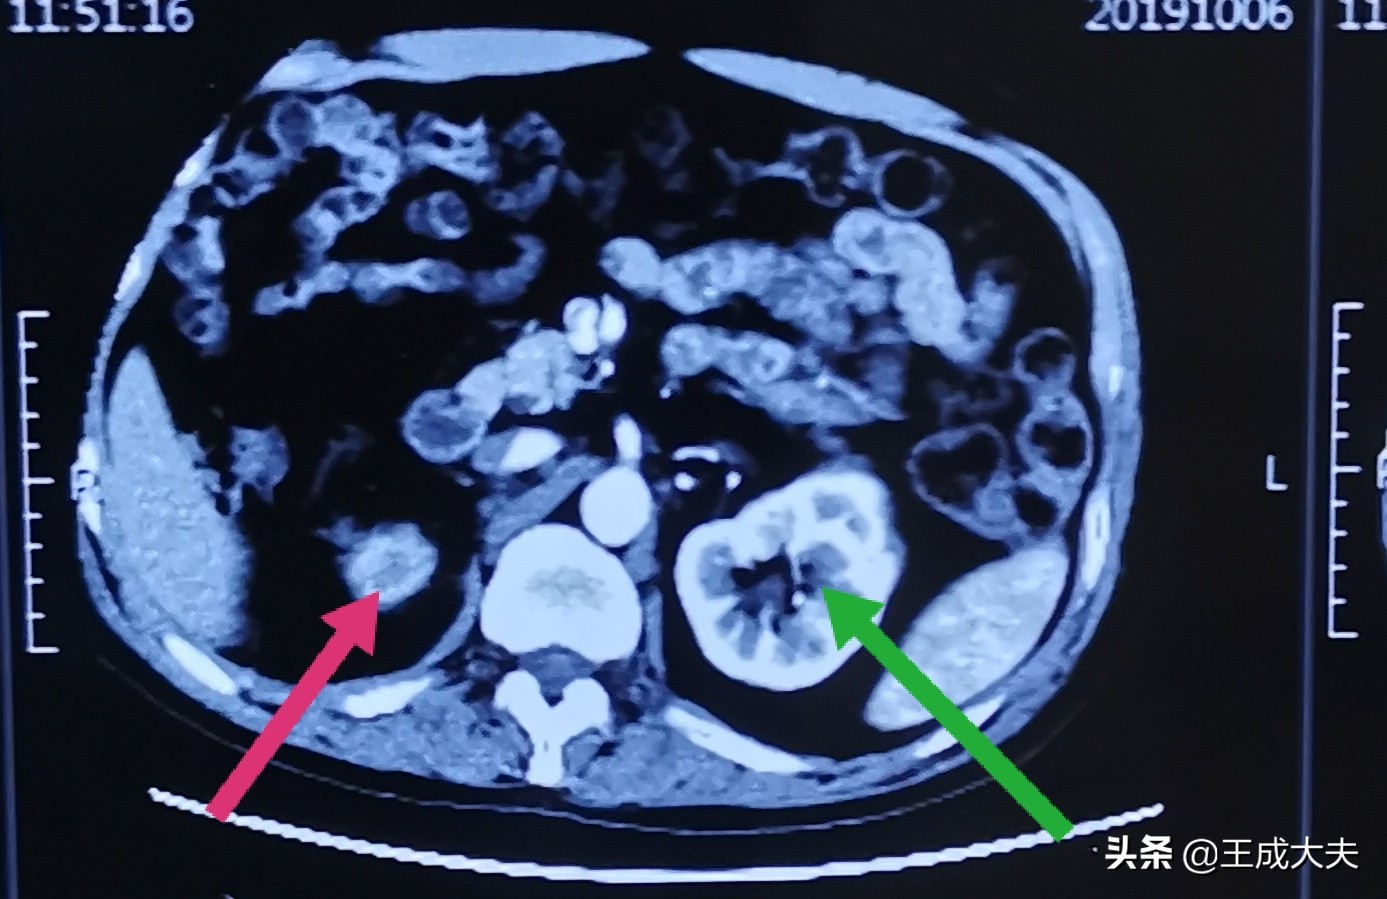

做CT提示:右侧输尿管结石仍然存在,右肾已经萎缩!

红色箭头所指右肾萎缩,绿色箭头所指左肾正常